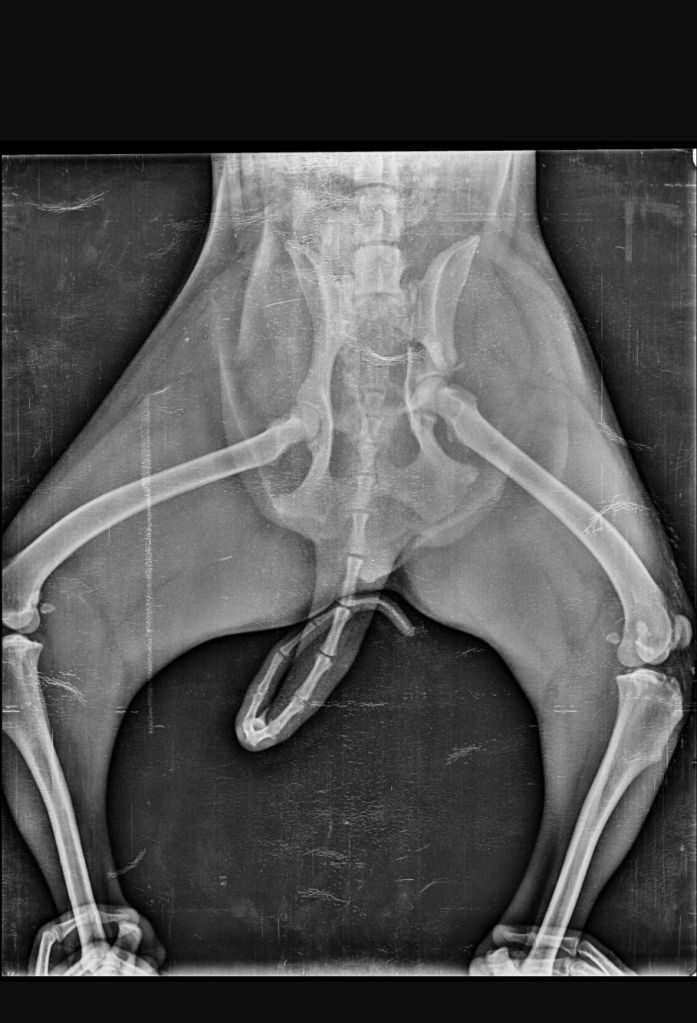

We had to rush him into an emergency and ensure the vets stabilized him. .. turns out he has a fractured hip and multiple injuries , one even on his penis π which bled so much.

He is still in a lot of pain and hence on heavy medication and sedatives.. we will know more about his injuries once all the swelling subsides…